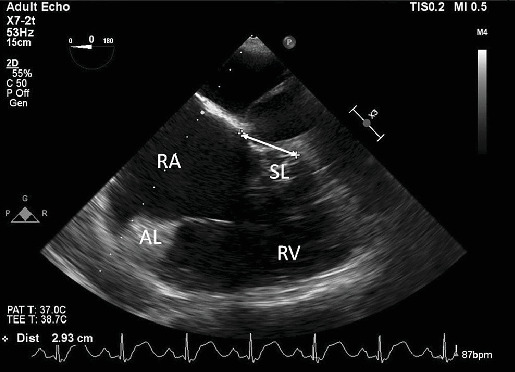

Abstract Image